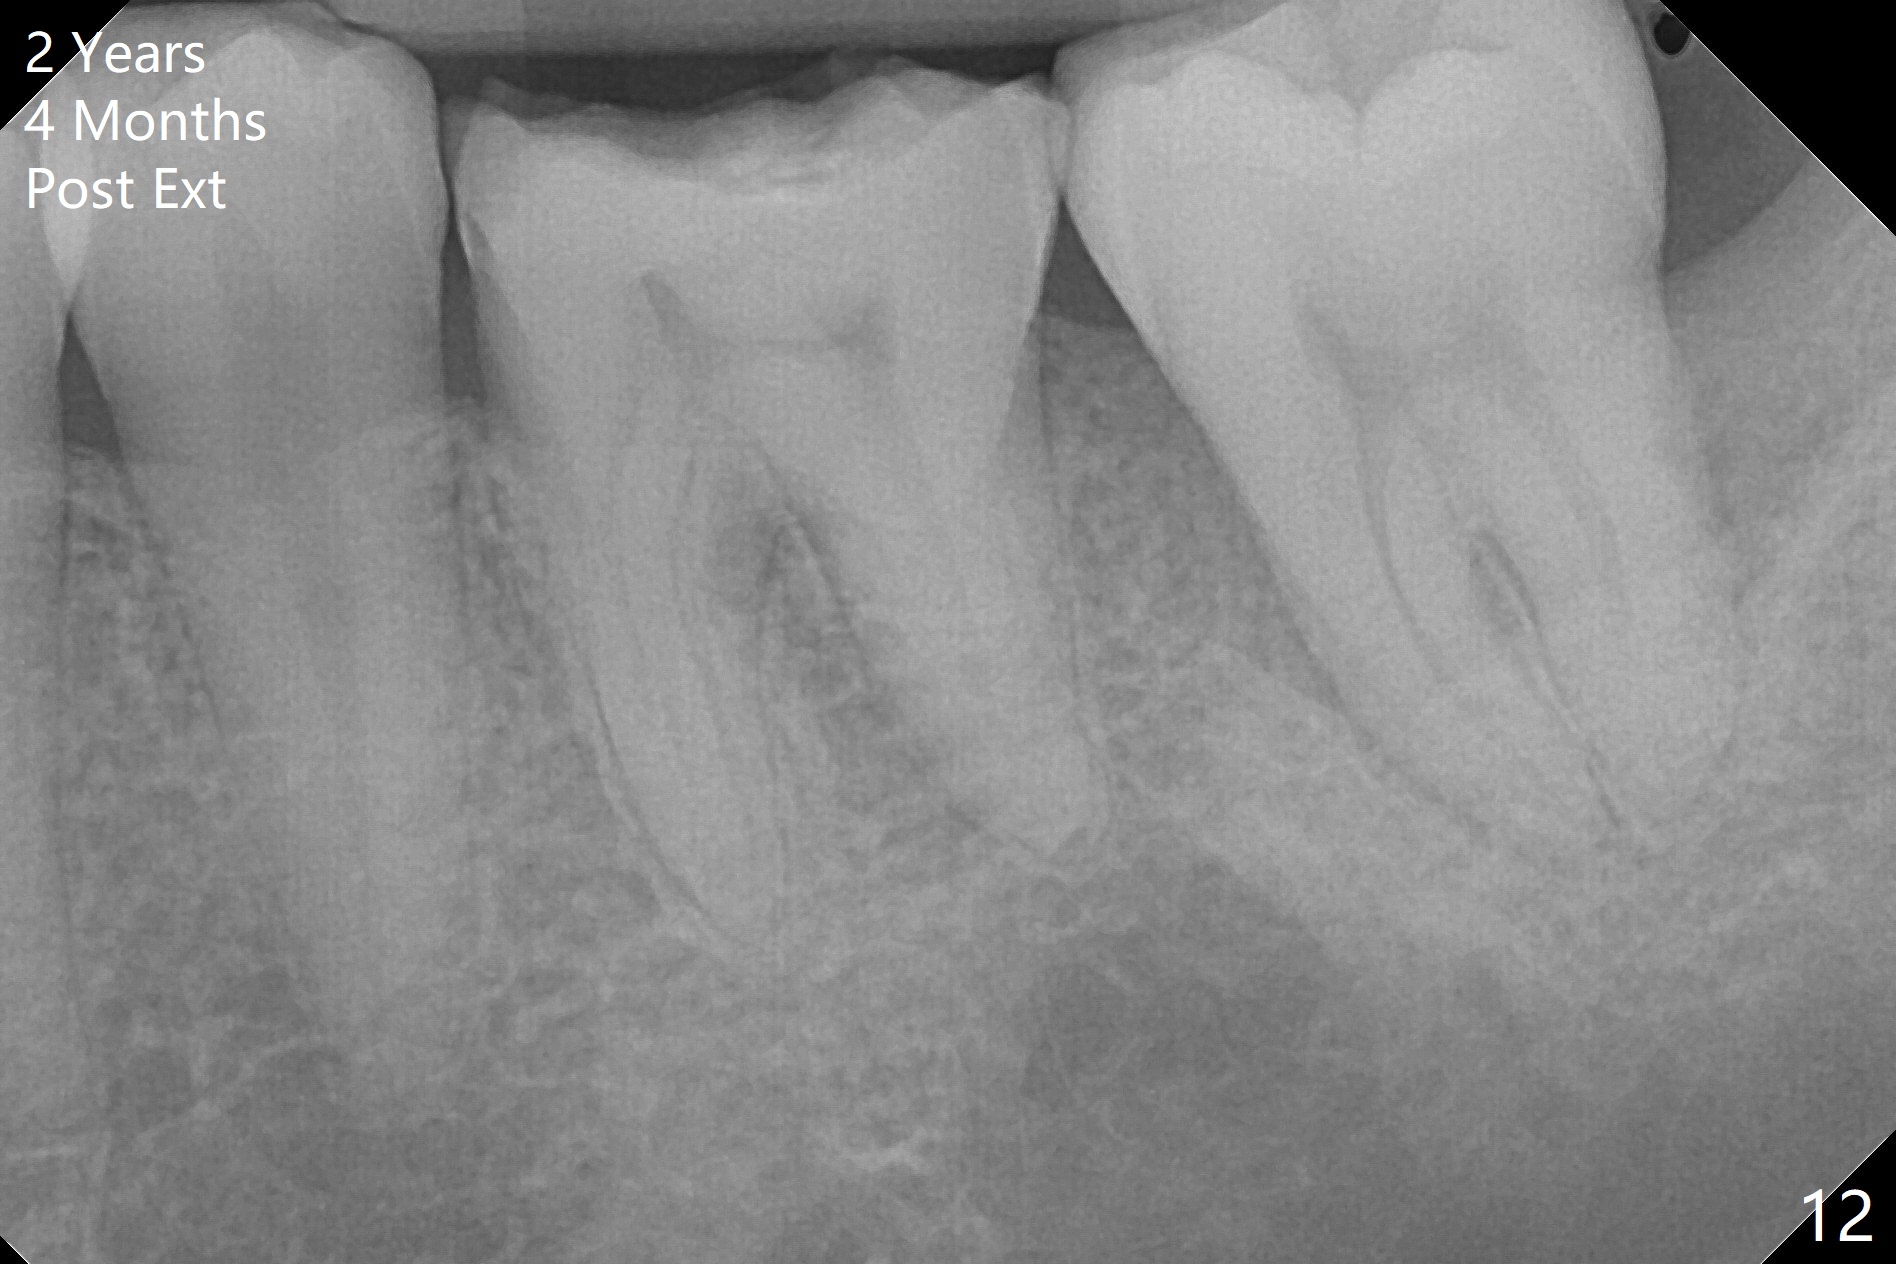

Photos are taken to show occlusal wear (bruxism) of the teeth #31 and 17 (Fig.7,8) prior to #17 extraction. Osteogen plug is placed in #17 socket after extraction and SRP at #18. The bone height at #18 distal seems to increase 2 years 4 months post extraction (Fig.9-12). The 1st molars have enamel hypoplasia with occlusal wear. In addition, occlusion is abnormal. There is no centric occlusion, partially contributing to periodontitis at #15 and 18. Crown is planned at #19 because of loss of occlusal amalgam (Fig.11 A, 12). Orthodontics may be required, although 2 insurances do not have orthodontic coverage for adults.